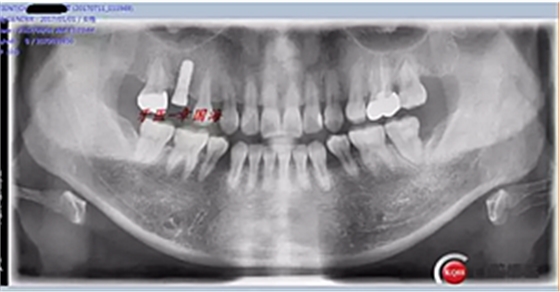

附另外一種植前后圖: